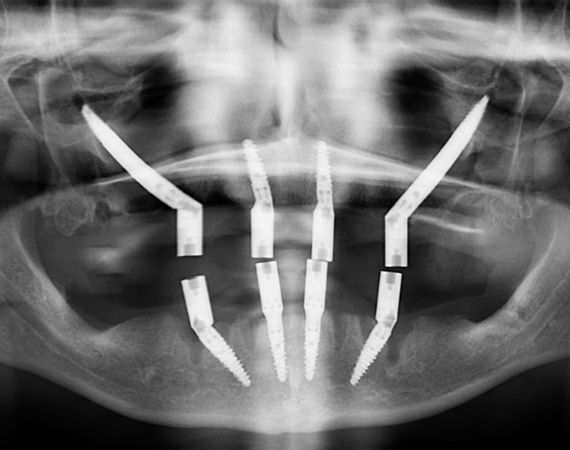

Implante Zigomático

A diferencia de los implantes convencionales, que se colocan directamente en el maxilar, los implantes zigomáticos se insertan mediante una intervención quirúrgica que atraviesa o bordea el seno maxilar para alcanzar el hueso cigomático. La colocación requiere un estudio previo con imágenes 3D (como una tomografía CBCT) para planificar con precisión la longitud, la dirección y la posición de los implantes.